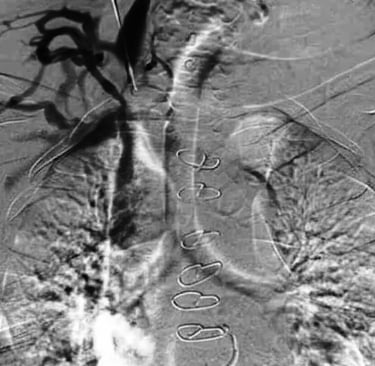

Flebografía de la vena ácigos en presencia de estenosis cavoatrial

Estenosis de la vena yugular con dilatación de sus efluentes